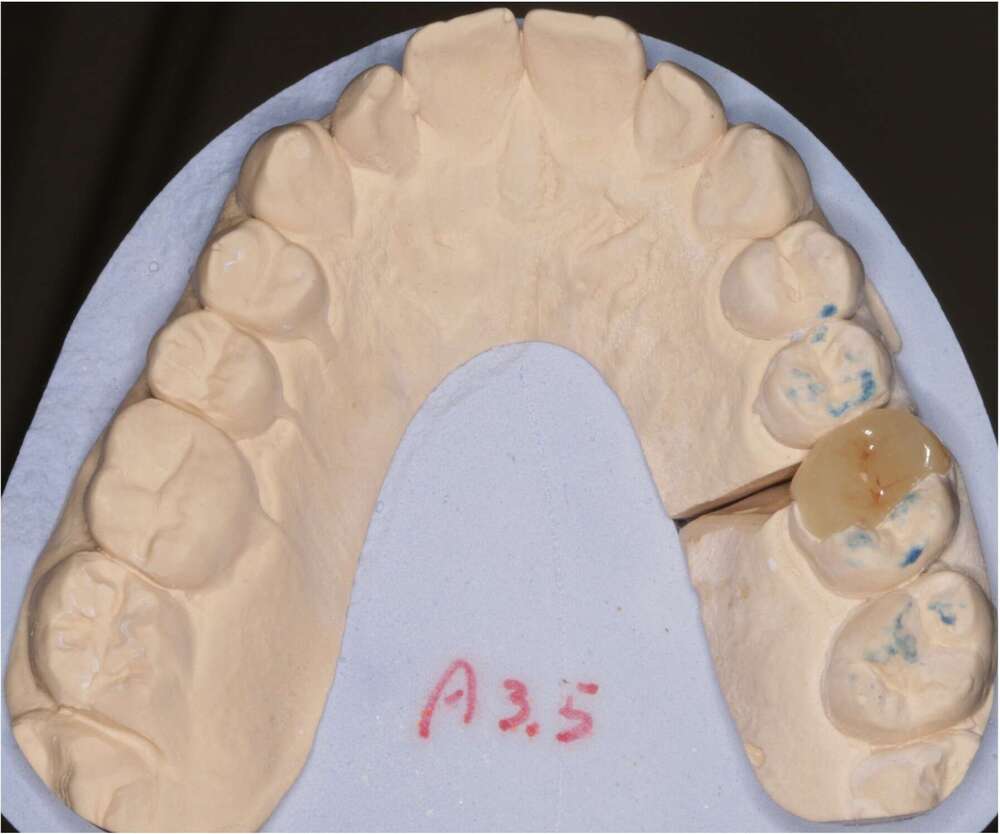

Onlay céramique

Réalisation d'un onlay en céramique par le laboratoire

Après essayage, le collage de L'onlay est réalisé.